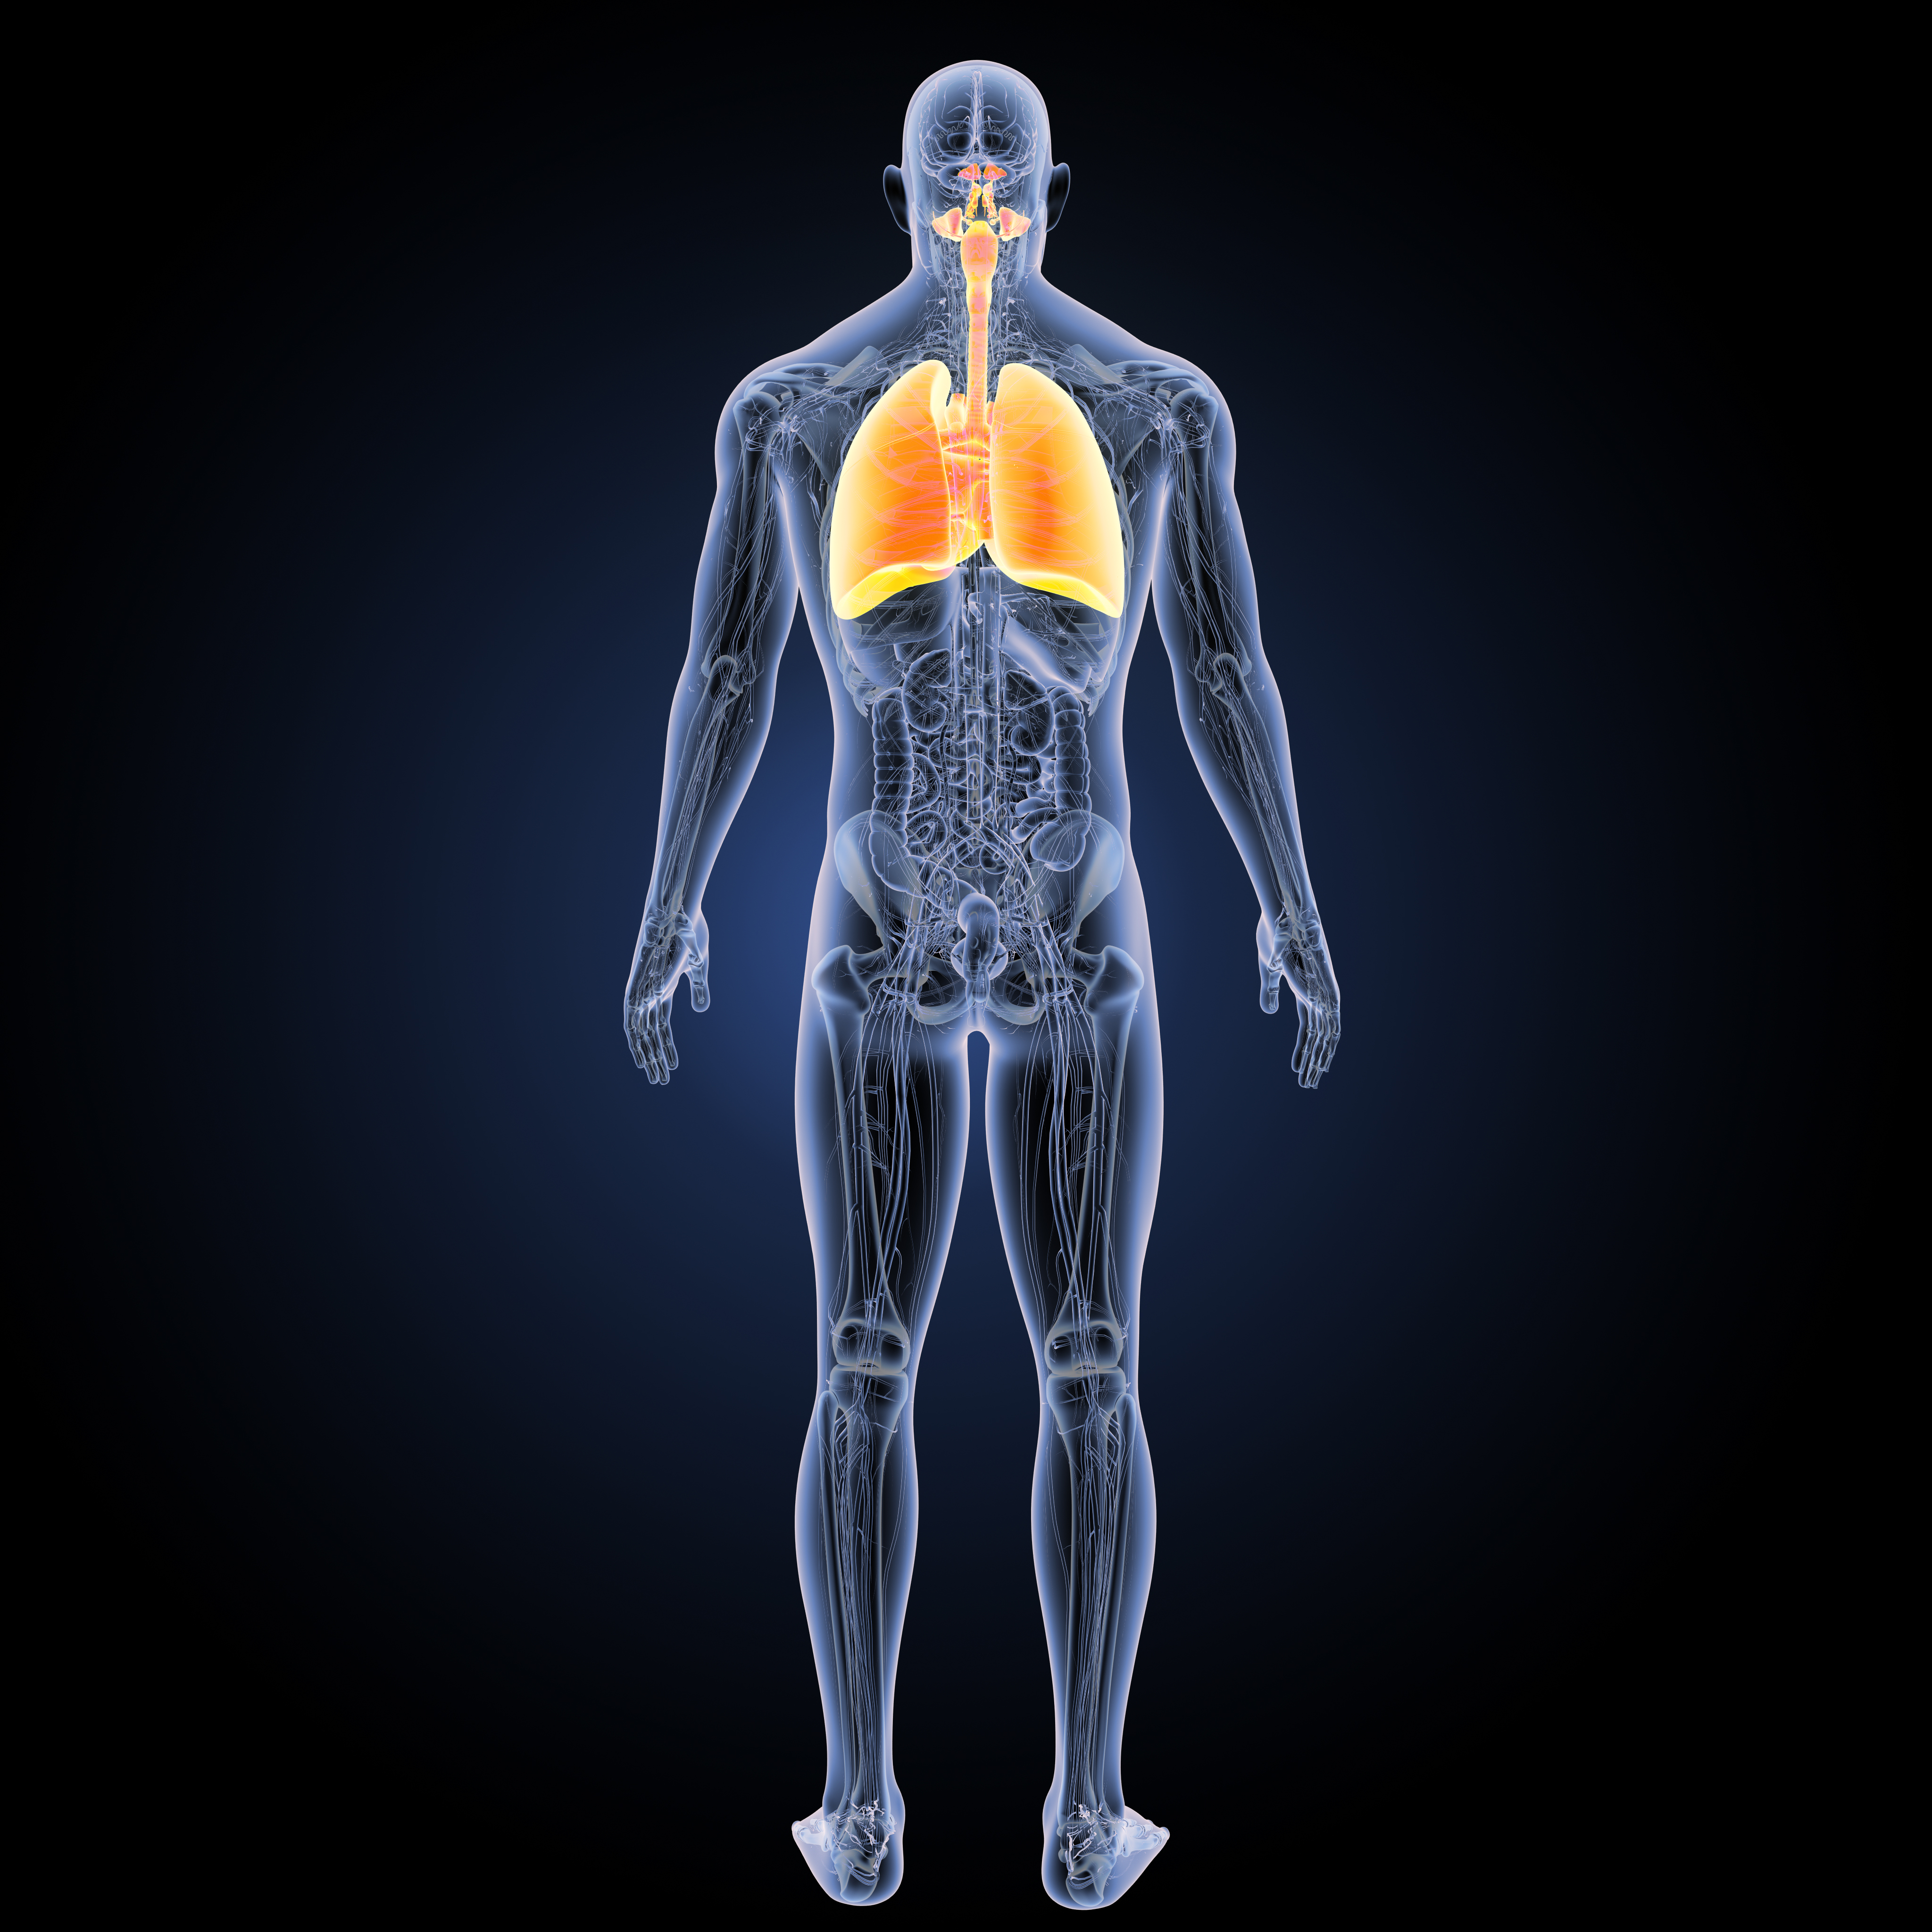

1. Lung Cancer

Lung cancer kills many people each and every year. Wouldn’t it be nice to know you had it so you could treat it before it becomes worse?

According to a study, lung cancer elicits volatile organic compounds, which can be detected by a breath analysis.